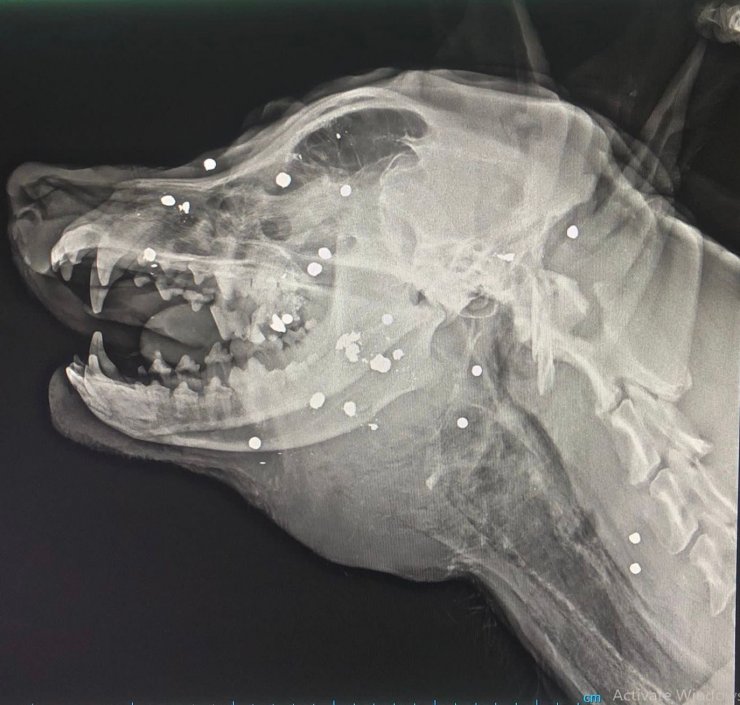

Olay, 5 Ağustos sabahı, Tekkeköy ilçesi Aşağıçinik Mahallesi'nde meydana geldi. Sosyal bilgiler öğretmeni Damla Özer, Rottweiler cinsi, 2 yaşındaki "Haşin" adlı erkek köpeğini sokakta kanlar içinde buldu ve veteriner kliğine götürdü. Müdahale edilen ve çekilen röntgeninde av tüfeğiyle yakın mesafeden ateş edilip, vurulduğu anlaşılan köpek öldü. Şikayet ve suç duyurusu üzerine polisler, tüfeği ateşleyen kimliği belirsiz kişiyi bulmak için çalışma başlattı. 30'a yakın tüfek saçmasının başına isabet etmesi sonucu öldürülen köpeği için mezar hazırlayan Özer, şüphelinin bulunmasını ve en ağır cezayı almasını istedi.

Yaşananları anlatan ve köpeğinin mahalleli tarafından da çok sevildiğini belirten Damla Özer, "Çok uysal, sessiz sakin bir köpekti, havlamazdı bile. Hep evin çevresindeydi. Kan revan içindeydi. Babamla birlikte en yakın veteriner kliniğine götürdük. Röntgen çekildi, kan tahlili yapıldı ve sonucunda vurulmuş olduğunu söylediler. Biz şok olduk. Hiç böyle bir şey beklemiyorduk. Birkaç saat sonra da öldüğünü öğrendik. O herkes için bir köpekti belki ama benim için bir çocuktan farksızdı. Evladım gibi bakıyordum ona. Evlat acısı gibi çok zor" dedi.